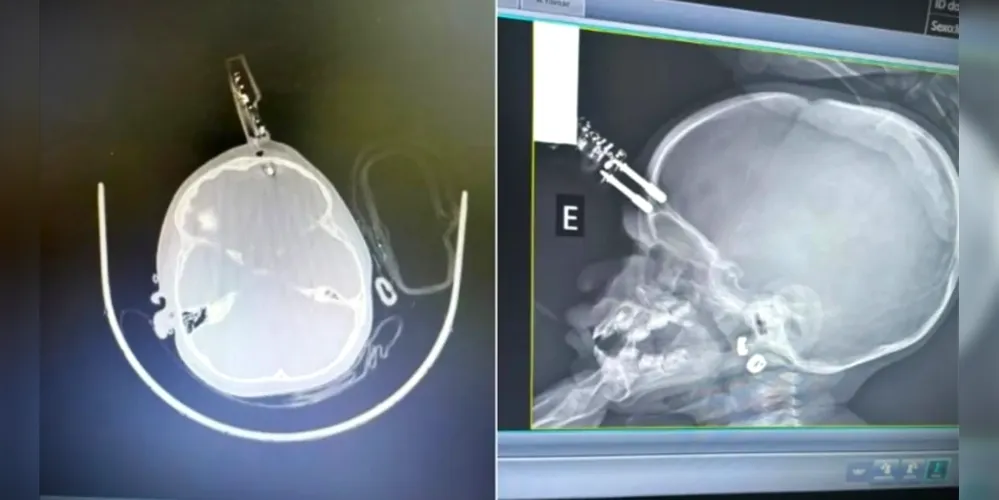

Após o portal aRede divulgar o drama da família de João Renato Matoso, de 26 anos, após um acidente sofrido por ele no dia 9 de abril na região da Vila Estrela, a família do motorista do Chevrolet Celta que teria a causado a colisão, ocorrida na rua Nestor Guimarães, entrou em contato para rebater a versão dada pela cunhada do motociclista, Joyce Kelly.